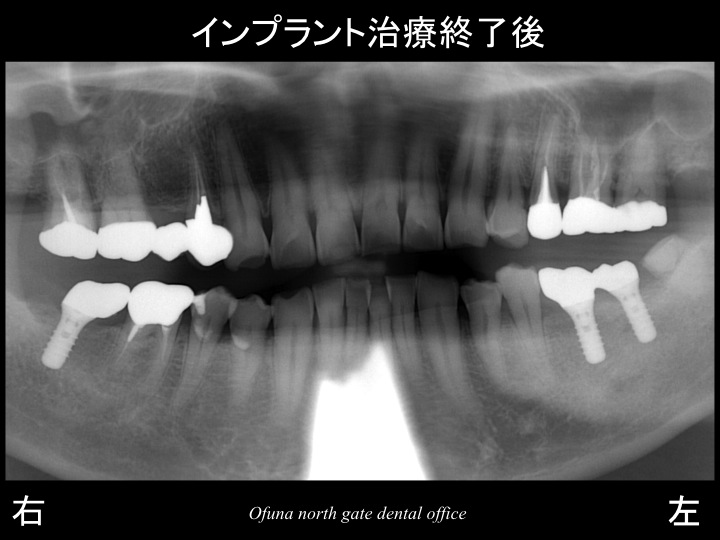

右下の奥歯と左下の奥歯の被せ物が取れてしまったため、

『奥歯で物が噛めない!』との問題から当医院を受診されました。

診査をすると被せ物が取れた歯は、虫歯が非常に深い状態でした。

これらの歯は神経がない歯です。

治療計画としてまず、虫歯の深い歯は保存不可能であったため、抜歯としました。

抜歯後は、下顎の左右の奥歯が欠損してます。

以下がインプラントの治療計画です。

今回の患者様は、下顎の左右奥歯が欠損したこの時点で

欠損部位にインプラント治療を行ったことが多きなポイントです。

欠損部にインプラントを埋入することにより、噛み合わせの安定が得られます。

これにより神経がない歯への負担を最小限にすることが可能になります。

簡単なケースでしたが、将来的なことを考えれば

インプラント治療は非常に有効な治療方法でした。